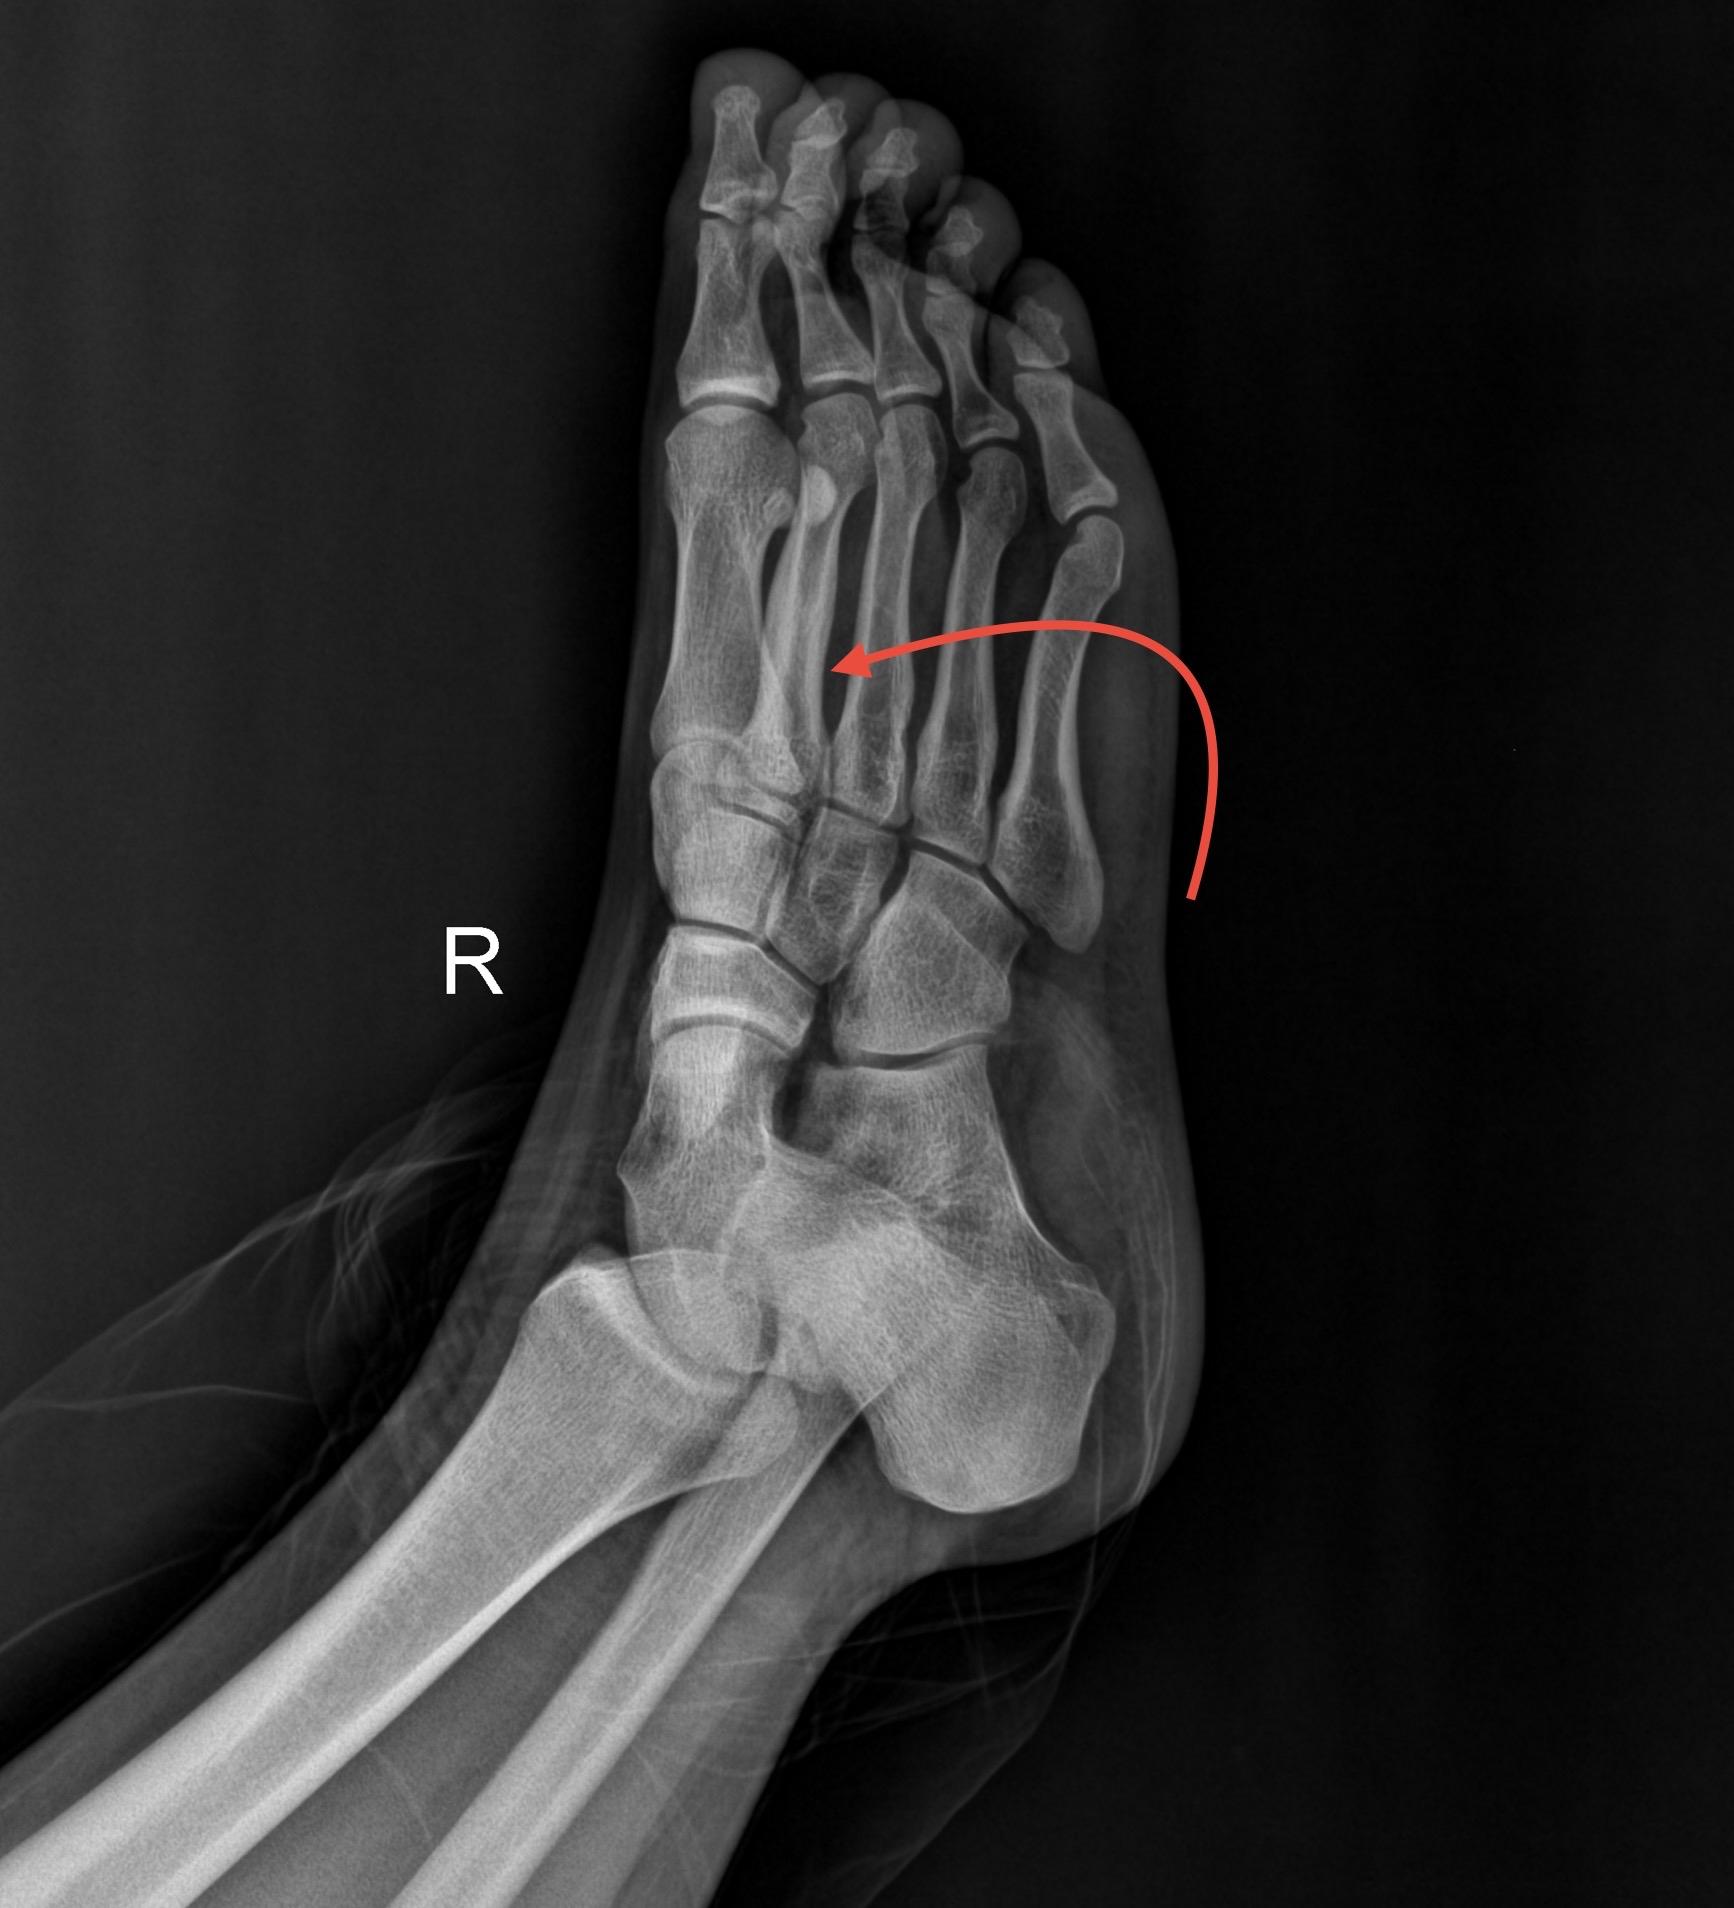

【骨肌】爱运动的烦恼!男,15岁,双侧足底部隐痛,爱好运动,喜欢长跑与打羽毛球!

男,15岁,双侧足底部隐痛,爱好运动,喜欢长跑与打羽毛球!